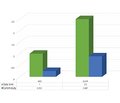

Рівень ацетилхолінестерази в сироватці крові до та після резекції в пацієнтів із хворобою Гіршпрунга

Illona Okvita Wiyogo (1), IGB Adria Hariastawa (1, 2), Munawaroh Fitriah (1, 2), Fendy Matulatan (1, 2)

(1) - Universitas Airlangga, Surabaya, East Java, Indonesia

(2) - Dr. Soetomo General Academic Hospital, Surabaya, Indonesia